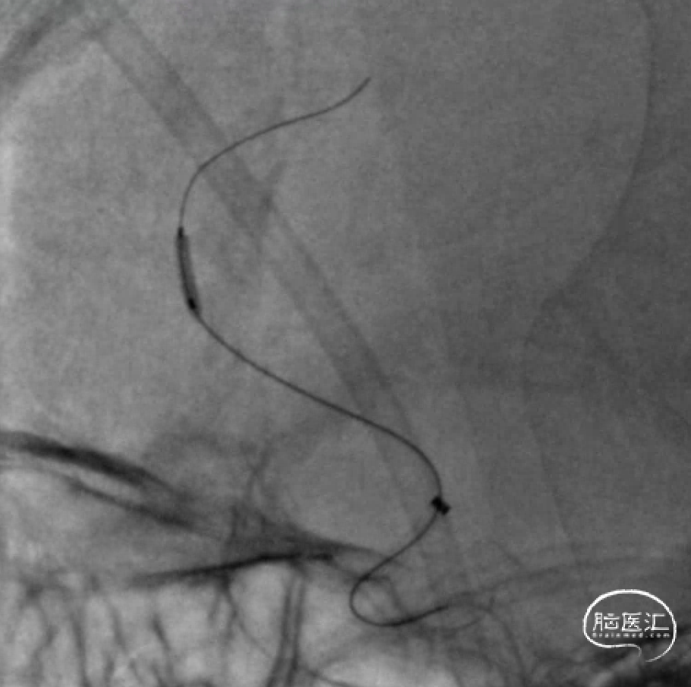

长鞘+125cm单弯+1.5m泥鳅导丝。

125cm Tethys®中间导引导管+2m 0.014inch+18微导管。

尝试通过闭塞段。

4mm×20mm取栓支架。

支架锚定后跟进Tethys®中间导引导管。

取栓后即刻造影。

15min后复查造影,明显回缩。

加奇SacSpeed®球囊扩张导管2×9mm顺利到位。

缓慢扩张至5atm后造影。

15min后复查造影,血流维持可。